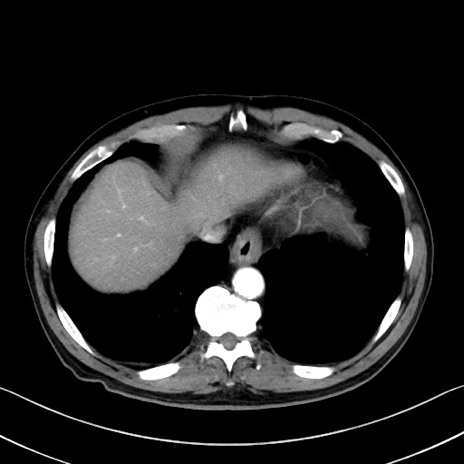

症例35(横断像)

【症例】70歳代 男性

【主訴】腹部膨満、嘔吐

【現病歴】昨日より腹部膨満感出現。本日増悪し、仙痛出現。嘔吐あり、受診。

【既往歴】糖尿病、胆摘後

【身体所見】BP 149/80mmHg、HR 74/min、BT 35.9℃、腹部:膨満、軟、圧痛なし。腸雑音減弱あり。上腹部正中切開瘢痕あり。

【データ】WBC 13500、CRP 1.72